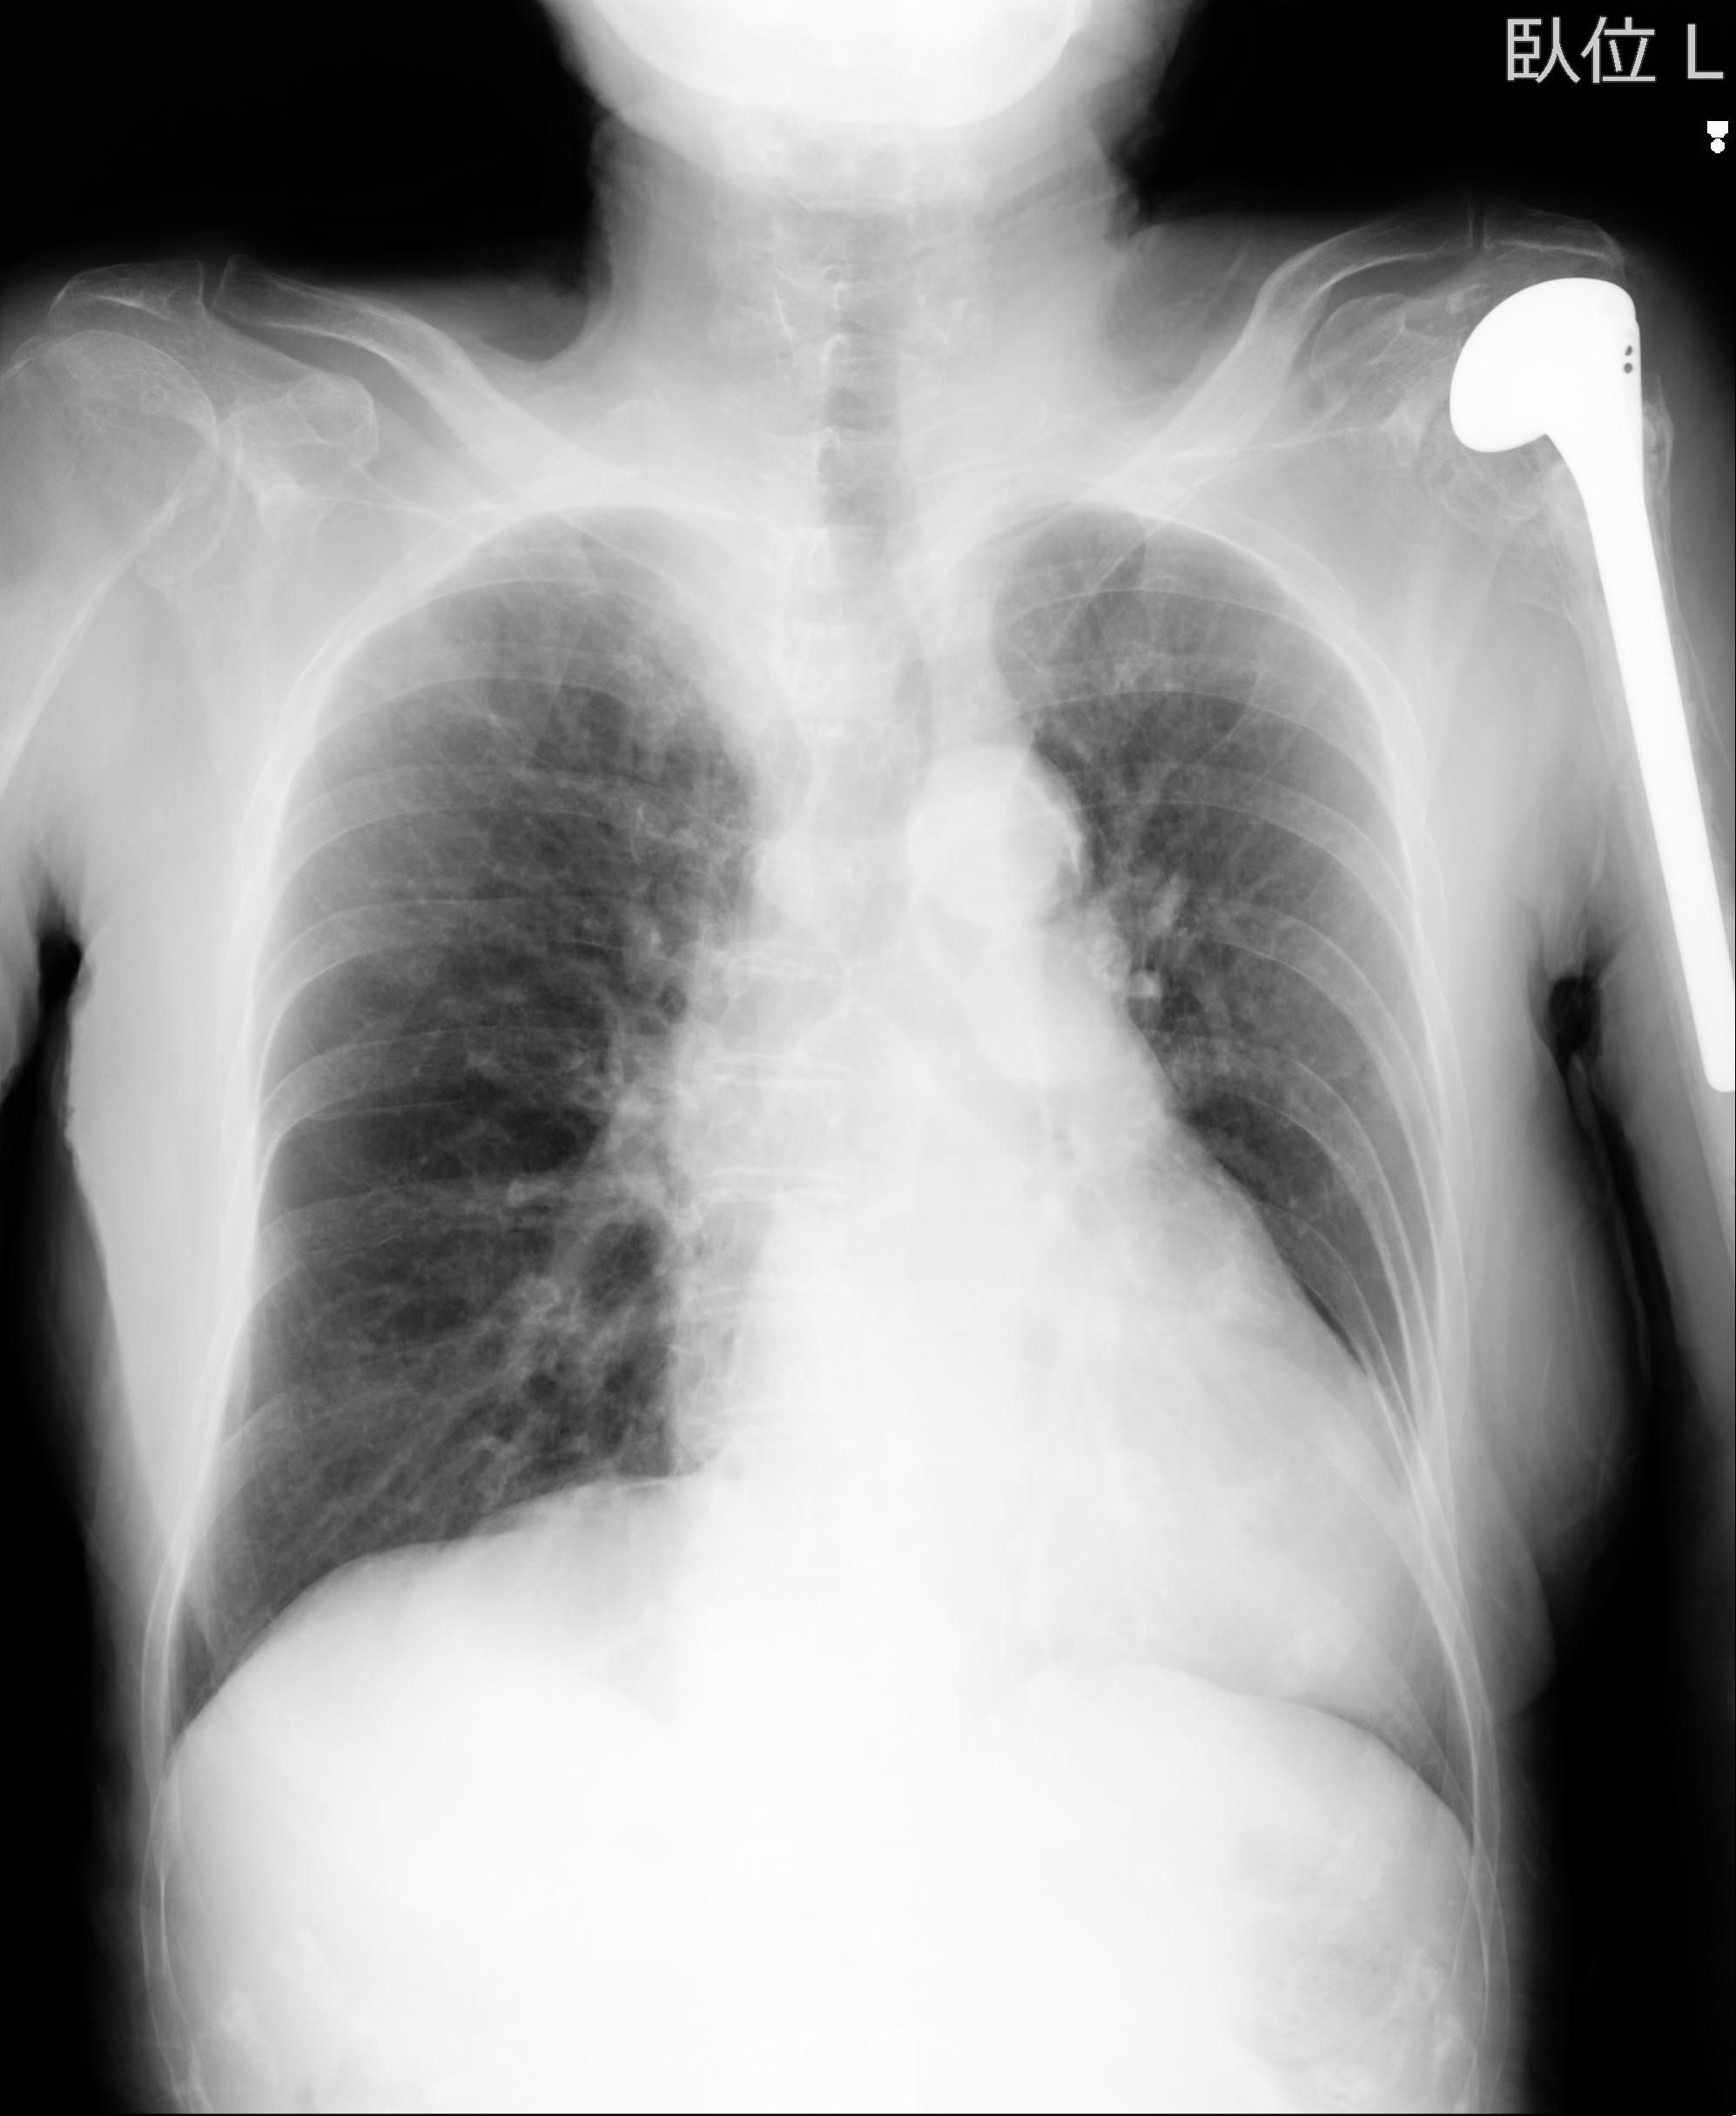

110214 12/20 肩 2R 12/21 肩 4R 72歳女性 左上腕外科頚プレート